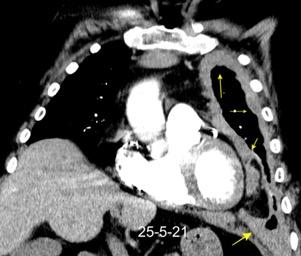

Síndrome de afectación postcardiaca (postcardiac injury)

Post infarto 1-7 % (Dressler)

Trauma cerrado Implantación marcapasos

Cirugía cardiaca. 17-31% (Post.pericardiotomía)

3707 pacientes 29 Derrames (0,78%) > de 25% del hemitórax

Todas menos 2 Izdos.

Angioplastia

By-pass coronario 21-10-03